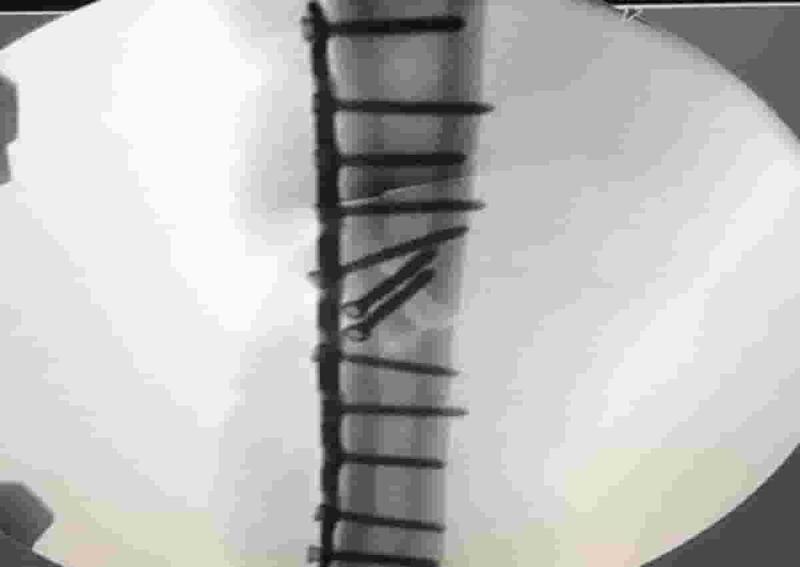

"Marc Marquez è stato operato 13 giorni fa e oggi è tornato in sala operatoria - ha dichiarato il dottor Xavier Mir -. La prima operazione ha avuto esito positivo, ciò che non era previsto era che la piastra fosse insufficiente. Un accumulo di stress nell'area operata ha causato alcuni danni alla piastra, quindi oggi la piastra in titanio è stata rimossa e sostituita da una nuova. Il pilota ha sempre seguito i consigli del medico e le sensazioni del suo corpo. Ora dobbiamo aspettare 48 ore per capire i tempi di recupero".

Una scelta, quella di applicargli una placca piuttosto che un chiodo, che era stata messa in discussione anche dal dottor Claudio Costa e dal dottor Matteo Lombardi, specialista che abbiamo interpellato più volte nelle ore successive all'intervento, ma che era stata suggerita dalla necessitá di ispezionare il nervo radiale e, soprattutto, di non stressare ulteriormente una spalla giá operata.